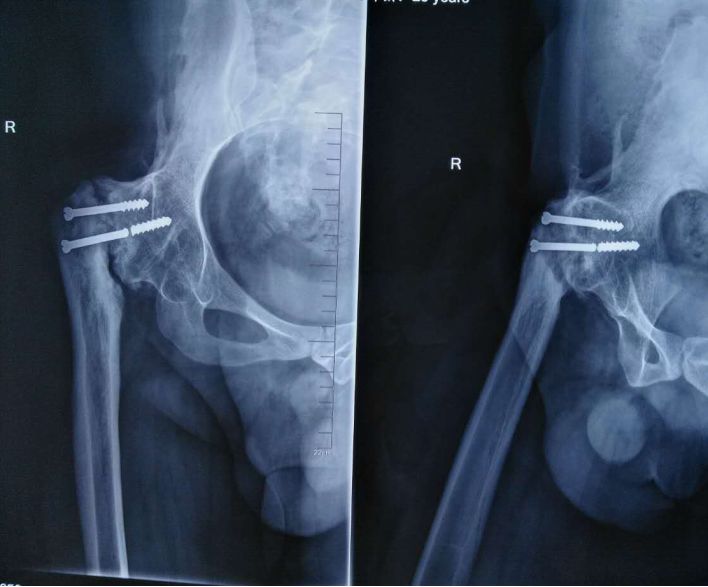

55岁手术后次日下地走路,45天愈合(具有临床愈合特征和X光愈合特征)这是愈合时间最短的股骨颈骨折

髓内钉与骨的过度处应力集中

• 股骨近端骨折禁止应用钢板

此处应用钢板有两种情况一是不会使用髓内固定,设备条件达不到;再就是理念落后见的病例少,交流少。此处外侧全部是长应力,钢板为张力钢板,内收肌力量强大,目前的钢板不能承受反复的弯曲应力,金属疲劳断裂失败率高,以下病例切开,钢丝捆绑进一步骨膜剥离,破坏了原始血肿,干扰骨愈合,都是失败原因